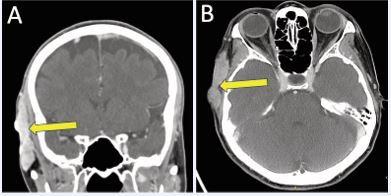

Three years later, serial imaging demonstrated increased thickening and enhancement along the right temporalis fascia. These findings continued to progress over the next six years with several enlarging subcutaneous nodules, which ultimately coalesced into a painful, 6 cm multilobular lesion along the right temporal scalp abutting the temporalis muscle and extending to the cutaneous surface without bony invasion, as demonstrated on contrast-enhanced head CT (Figure 1).

Figure 1 Contrast-enhanced CT head demonstrating right temporal scalp recurrence in A) coronal; and B) axial planes.